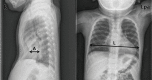

Methods: Consecutive 99 patients who had undergone BR for PE in a single hospital from March 2012 to June 2017 were included in the present study. Severity of PE is presented as a radiographical Haller index (RHI) in the present study. RHI is calculated by the ratio of the transverse diameter to the anteroposterior (AP) diameter at the point of the deepest chest wall depression. Patients with a ≥3.5 RHI value, which simultaneously increased to more than the value of RHI before BR, were considered as demonstrating recurrence in the present study. Follow-up data after BR were collected at subsequent time points (i.e., immediate before and after, one month, sixth months, and one year after BR). All postoperative chest wall changes were analyzed to find out the difference according to the age at the time of the Nuss procedure (NP) [<10 years old (early group; EG) vs. ≥10 years old (late group, LG)].

Results: The mean age of patients was 8.91 (±5.23) years at the age of the NP and the mean duration of bar placement was 28.4 (±5.04) months. Seventy-eight males and 21 females were included. The pectus type was 79 symmetric and 20 asymmetric cases. The mean observation period after BR was 16.47 (±3.74) months. There was a significant correlation between the Haller index using chest CT and simple radiography data (P<0.001). Irrespective of the age groups, there were a significant decrease in RHI values after the NP (both P<0.001). In addition, there were no differences in RHI values between the EG and the LG cohort before the NP and immediately after the NP (P=0.775, P=0.356, respectively). RHI values was significantly decreased in the EG (P=0.040) and increased without a significance in the LG (P=0.330) during bar placement. The chest wall depression progressed for the first six months after BR. However, the chest wall depression did not progress one year after BR. Recurrence occurred in nine cases at one year after BR (four cases in the EG and five cases in LG). The recurrence rate was higher in the LG than in the EG without a significance (P=0.479). Multivariate analysis of the recurrence revealed that only RHI after the NP was identified as an independent risk factor of the recurrence. ROC study also showed that RHI value after the NP had a significant predictable cutoff value for the recurrence [cutoff value of RHI: 2.91, sensitivity: 88.9%, specificity: 90.0%, P<0.001, area: 0.899, 95% confidence interval (CI): 0.806-0.993].